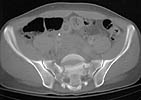

A 28 year old male jumped from the 4th floor on 11-25-2000 sustaining an L1 burst fracture that has been fixed anteriorly by the neurosurgeon with a strut between T12 and L2. A Kaneda device was placed anteriorly as well. My concern is the pelvic ring injury. There are bilateral sacral fractures through the foramen and a transverse element through the sacrum between S2 and S3. the lower part of the sacrum is displaced forward. Anteriorly there are right superior and inferior pubic rami fractures.

CT1

Axial